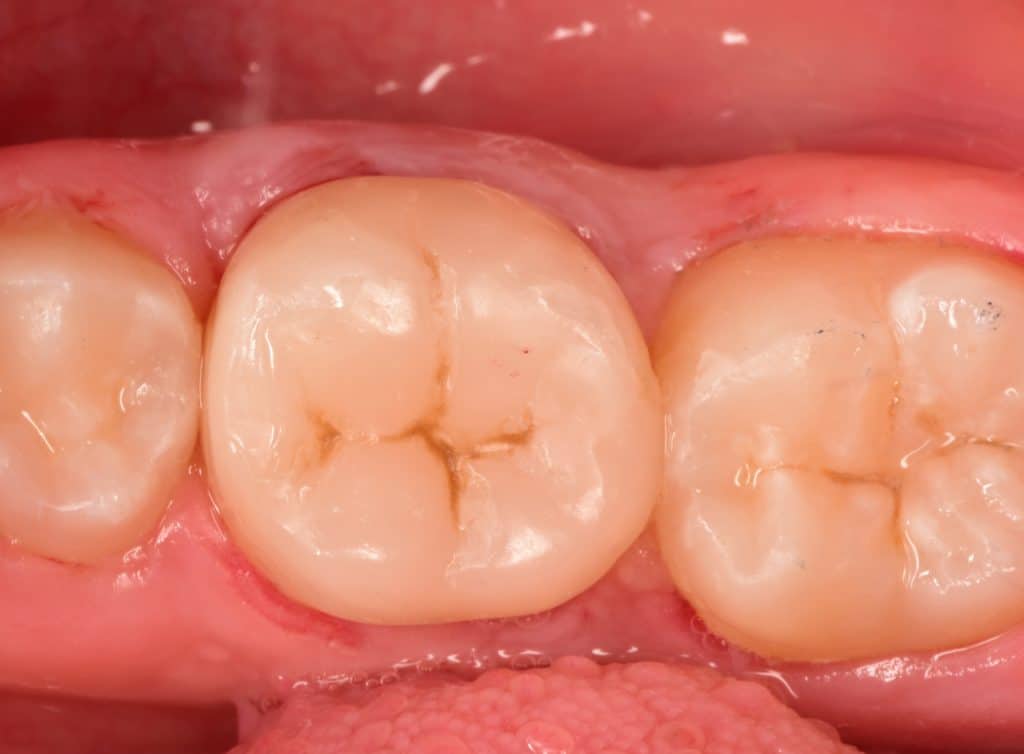

Final result after checking the high spots

Final result